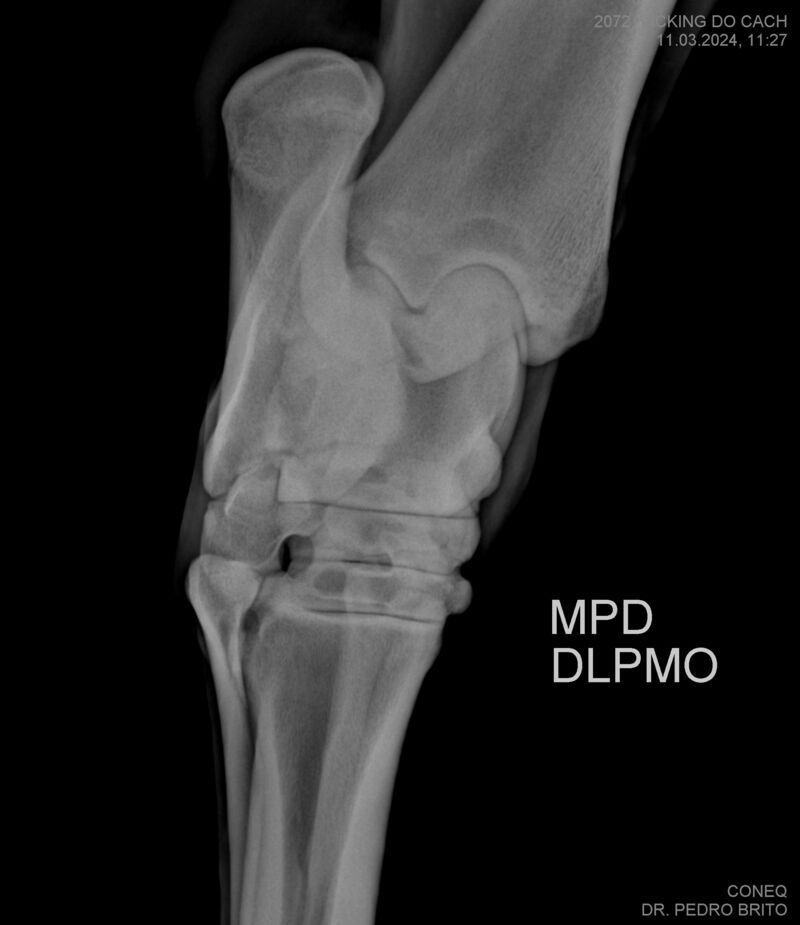

VIKING DO CACH